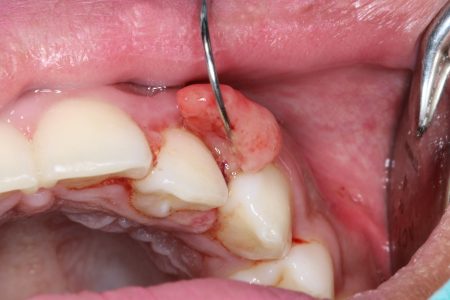

Oral pathology involves the diagnosis and management of abnormal tissues in the mouth, jaws, or face. If you have a lesion, lump, ulcer, or other suspicious area, a biopsy may be needed to determine the cause and guide treatment.

• Soft Tissue Biopsy: Used for lesions on the gums, cheeks, lips, tongue, or palate.

• Hard Tissue Biopsy: Involves sampling from the bone, often for unusual growths or changes in the jaw detected through imaging.

When Is a Biopsy Needed?

We may recommend a biopsy for:

• Persistent ulcers or sores

• White or red patches that don’t resolve

• Unusual lumps or tissue thickening

• Bone lesions seen on x-rays or 3D scans